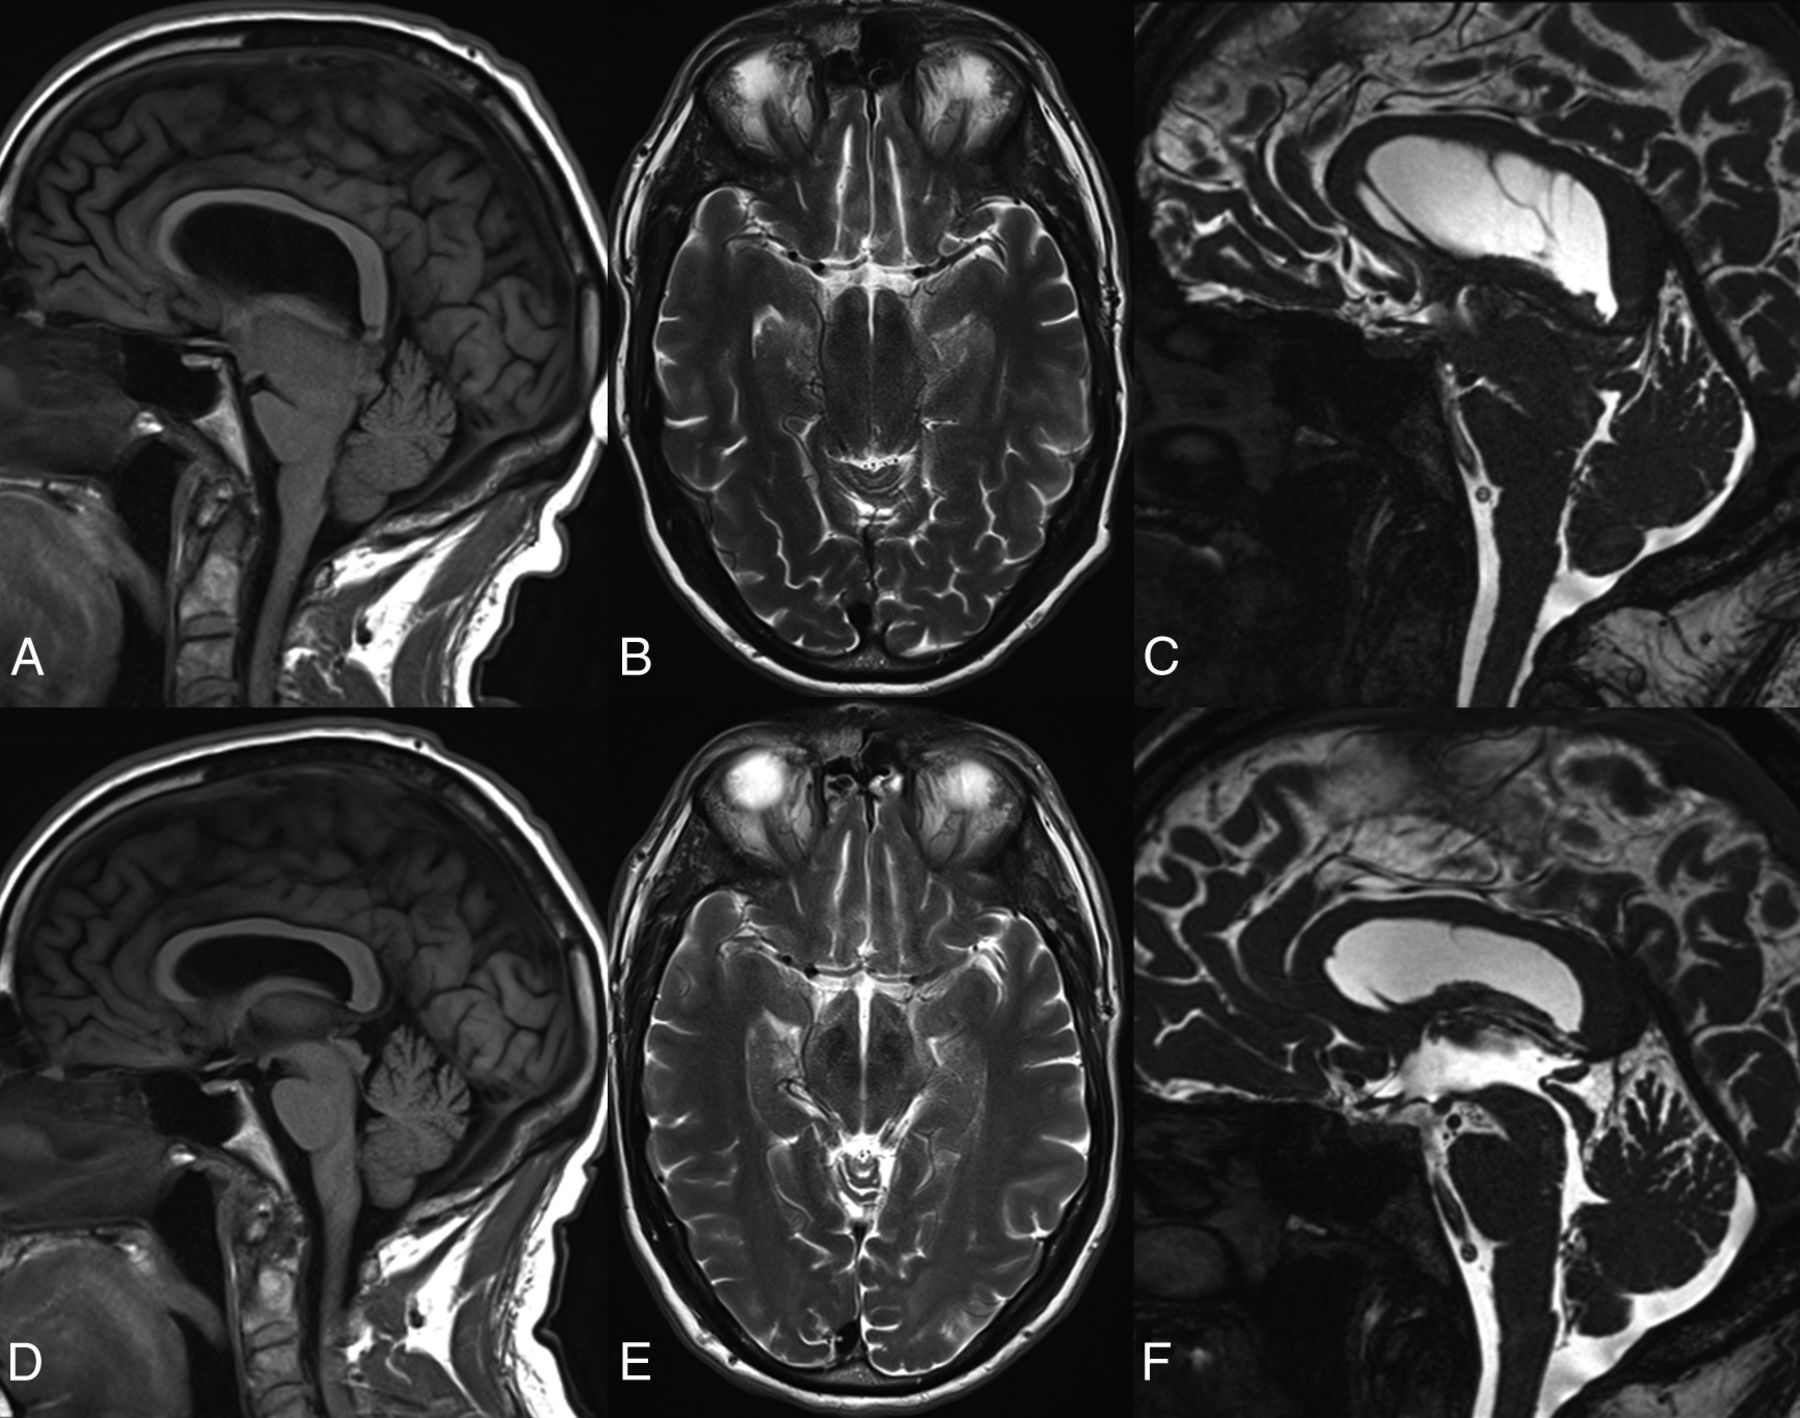

Pontomammillary distance on sagittal T1 (A–C) and anteroposterior midbrain diameter on axial T2-weighted MRI (D–F) in a healthy control (A and D), and patients with classic SIH (B and E) and atypical SIH (C and F).

All subjects were scanned with clinical 1.5T or 3T MR imaging scanners with clinical brain MR imaging protocols, including conventional pre- and postgadolinium T1-, T2-, and T2*- weighted sequences and an axial DTI sequence with 12 diffusion directions. The axial level of the midbrain was selected on 5-mm-thick axial T2 images oriented parallel to the line connecting the inferiormost points of the genu and splenium of the corpus callosum at the level showing the red nuclei. The average anteroposterior midbrain diameter (AP) and pontomammillary distance (PM) were combined in the Sagging Index = AP/PM (Fig 1), which was used as an imaging biomarker of the severity of brain sagging and not to diagnose SIH. The intraclass correlation coefficients for the 36 controls between 2 independent image readers were 0.86, 0.81, and 0.8 for the AP midbrain diameter, the PM distance, and the Sagging Index, respectively, indicating very good reproducibility. When available, spinal imaging (nuclear medicine cisternography, CT myelography, and/or whole-spine MR imaging) was assessed for determination of the site of CSF leak. Statistical analyses were performed with SPSS 21 (IBM, Armonk, New York). Nonparametric statistical analyses by using the Kruskal-Wallis or Mann-Whitney U test as appropriate were performed. Distribution of discrete variables between groups was assessed with the χ2 test. A 2-tailed P value <.05 was used as a statistical significance threshold.